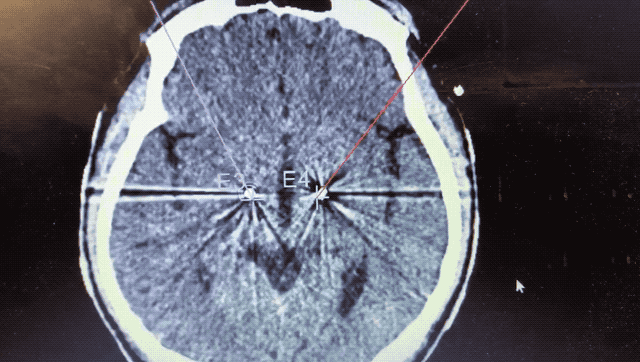

順利檢測(cè)到典型的核團(tuán)信號(hào)后,再次植入刺激電極到相應(yīng)位置,測(cè)試后即可完成單側(cè)的電極植入。對(duì)側(cè)只需借助機(jī)器人再次定位,并將檢測(cè)電極、刺激電極依次植入,最后,還需將刺激器植入患者胸前皮下。根據(jù)術(shù)后CT顯示,本手術(shù)雙側(cè)植入電極的位置與術(shù)前規(guī)劃路徑完全吻合,患者開(kāi)機(jī)后,起搏器會(huì)開(kāi)始沿刺激電極向患者核團(tuán)實(shí)施高頻電刺激,以減輕疾病癥狀,提高患者的生活質(zhì)量。

術(shù)后CT顯示雙側(cè)電極植入位置與規(guī)劃完全吻合